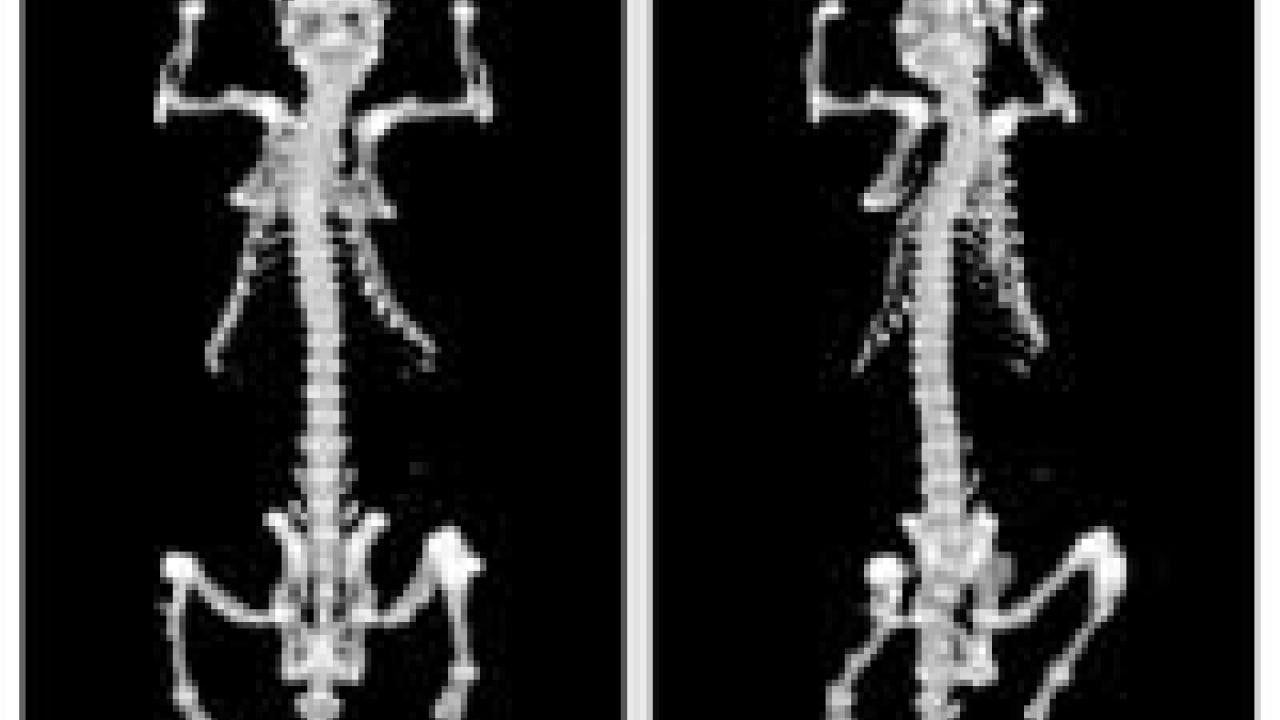

photo scan of two rat skeletons

This MicroPET scan of a live rat shows the skeleton.

The current machine, called MicroPET II, can resolve a volume of about one cubic millimeter, or one microliter, Cherry said. That represents an approximately eight-fold improvement over an earlier device built by Cherry's laboratory at UCLA, before moving to UC Davis in 2001.